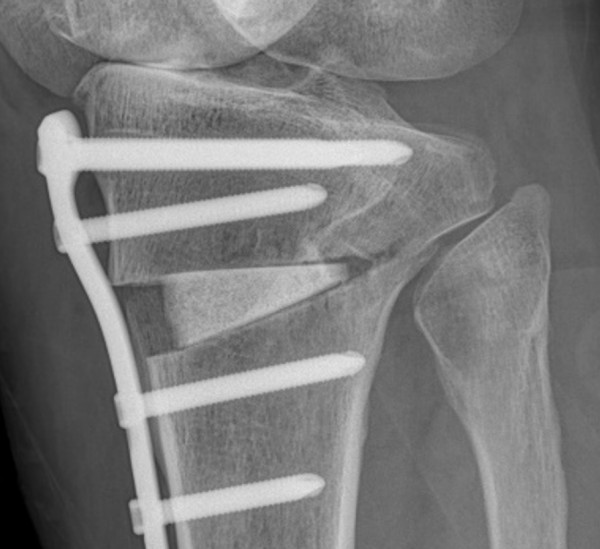

절골수술은 무릎 관절의 비정상적인 정렬을 교정하기 위한 수술적 방법입니다. 이 수술은 주로 관절염으로 인한 통증과 기능 장애를 겪고 있는 환자들에게 시행됩니다. 수술 과정에서는 뼈를 절단하고 재정렬하여 무릎에 가해지는 압력을 분산시킴으로써, 관절에 대한 스트레스를 줄이고 통증을 완화시킵니다. 이러한 접근법은 관절의 수명을 연장시키고, 궁극적으로는 관절 교체 수술을 피할 수 있게 해줍니다.